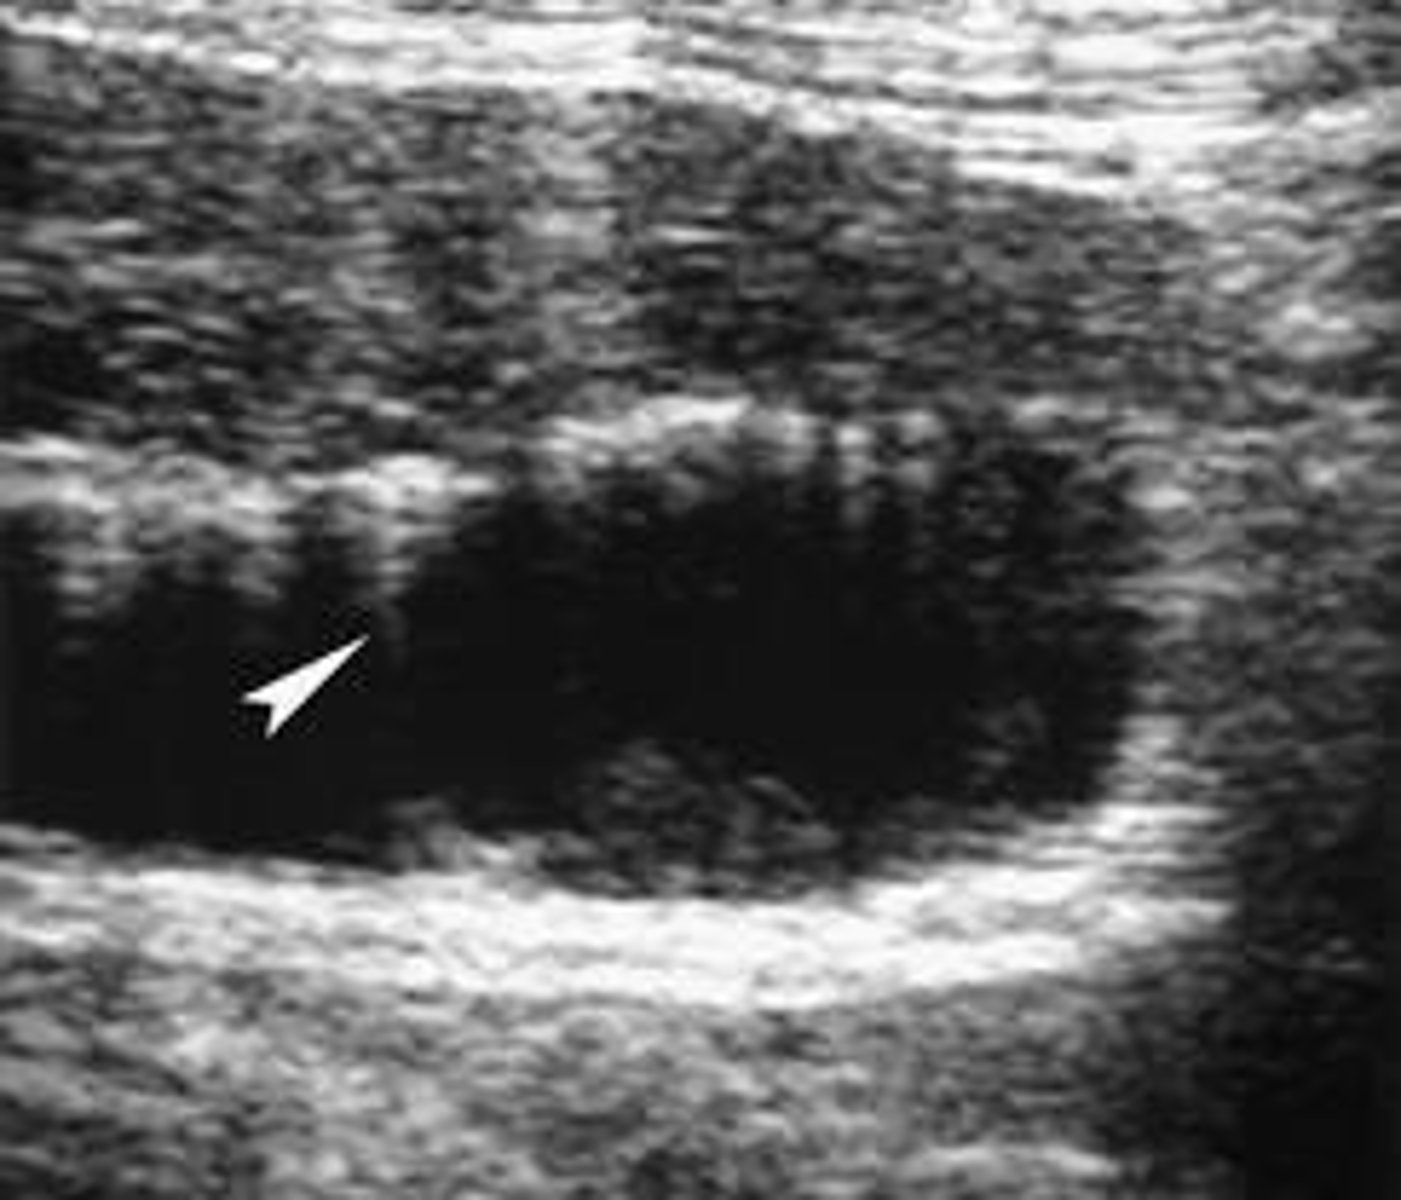

Sludge

- thickened/viscid bile that occurs from bile stasis

Sludge is composed of

Sludge sonographic findings

GB may be packed with sludge and difficult to distinguish from liver parenchyma because it will appear isoechoic (aka hepatization).

Prominet GB with amorphous, low-level echoes without posterior shadowing located in the dependent portion of the gallbladder

Sludge is gravity dependent- will move with change in patient position

tumefactive sludge is

sludge that mimics polypoid tumors/GB mass